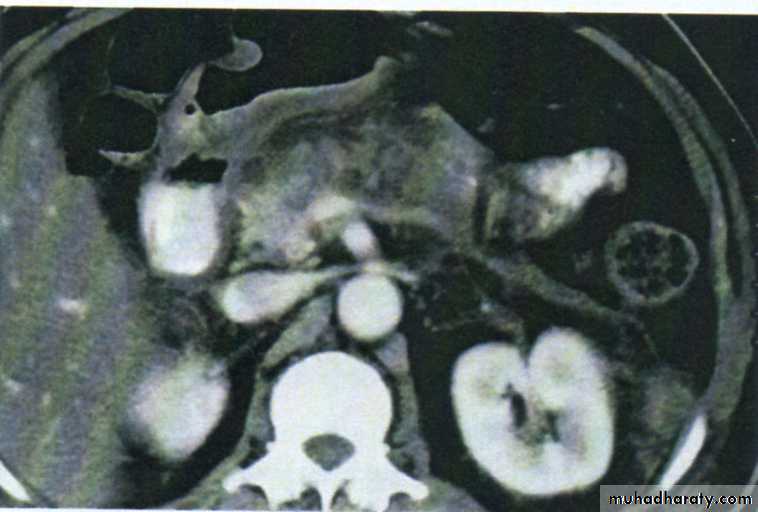

• Ultrasound and computerized tomography (CT) scanning are increasingly used to identify the cause of peritonitis Such knowledge may influence management decisions

• Ultrasound/CT scanning often diagnostic.

• Ultrasound or CT scanning is the investingation of choice and permits early detection of subphrenic collections